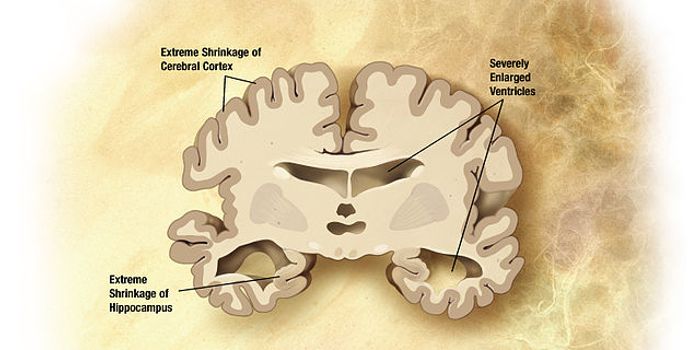

JUN 28, 2016NeuroscienceIn patients who suffer from any form of dementia, the loss of memory and other effects of the disease are devastating bo ...

JUN 16, 2016NeuroscienceAlzheimer’s disease (AD) currently affects 5.5 million people in the U.S. over the age of 65, and that number will ...

MAY 09, 2016NeuroscienceAlzheimer’s disease is the sixth leading cause of death in the United States. Currently 1 in 3 senior citizens (ov ...

APR 05, 2016NeuroscienceAlzheimer’s Disease (AD) is the most common form of dementia, currently affecting 5.5 million people in the U.S. T ...

JAN 18, 2016NeuroscienceAlzheimer’s disease (AD) and other forms of dementia are on the rise. There is no known cause of AD and there isn& ...

AUG 26, 2015NeuroscienceHealth researchers claim that there are now almost 47 million people living with dementia around the world, an increase ...